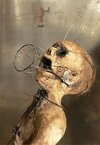

В 50х годах американцы в медицинских целях дали некоему художнику карандаши и ручки со словами «америка великая нация, сделай это, сынок, сделай ради своей страны…In God We Trust, понеслась»

Творцу вкололи ЛСД-25 и приказали изобразить врача, который, собственно, его и раскумарил.

Вот что из этого вышло в хронологическом порядке с некоторыми подробностями.

Через 20 минут после первого захода 50 мкг

Наблюдающий врач записывает — пациент рисует углем.

Со слов пациента:

«Состояние нормальное.. пока никаких эффектов».

В 50х годах американцы в медицинских целях дали некоему художнику карандаши и ручки со словами «америка великая нация, сделай это, сынок, сделай ради своей страны…In God We Trust, понеслась»

Творцу вкололи ЛСД-25 и приказали изобразить врача, который, собственно, его и раскумарил.

Вот что из этого вышло в хронологическом порядке с некоторыми подробностями.

Через 20 минут после первого захода 50 мкг

Наблюдающий врач записывает — пациент рисует углем.

Со слов пациента:

«Состояние нормальное.. пока никаких эффектов».